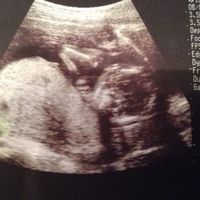

今17週の妊婦です エコー写真は16週5日のものですが もしどなたか性別 Okwave

Backyard 16週目 性別ほぼ確定 エコー写真有

男の子のエコー写真の 17週のエコーです。性別は男の子で確定でしょうか??? 早く分かれば名前決めたりしたいなあ どう思われますか?皆さんのエコーが見たいです 6月3日 お気に入り 妊娠17週目 性別 男の子 名前 エコー choco (3歳8ヶ月) コメント 6月 317週 性別 男の子 エコー 男の子の性別判定はいつから可能? 男の子の性別判定はいつから可能なのでしょうか? 男の子の性別判定は比較的早く、早くて15週・16週ごろからシンボルが見えてくる ようです!17週のエコーです。性別は男の子で確定でしょうか?早く分かれば名前決め 17週のエコーです。性別は男の子で確定でしょうか??? 早く分かれば名前決めたりしたいなあ♪ どう思われますか?皆さんのエコーが見たいです ️